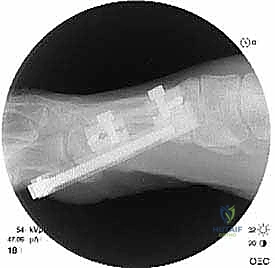

الخطوة الخامسة: التثبيت الداخلي القوي (Internal Fixation)

لضمان التئام العظم في وضعه الجديد والطويل، يجب تثبيته بقوة شديدة. يستخدم الدكتور هطيف أحدث الشرائح المعدنية التيتانيوم ذات الزاوية الثابتة (Locking Plates) والمسامير الدقيقة. هذا التثبيت القوي يمنع أي حركة بين العظام ويسمح ببدء العلاج الطبيعي في وقت مبكر.

بعد التأكد من الطول المثالي واستقرار التثبيت باستخدام الأشعة السينية في غرفة العمليات، يتم غسل الجرح بمضادات حيوية وإغلاق طبقات الأنسجة والجلد بخياطة تجميلية دقيقة لتقليل الندبات قدر الإمكان. يتم وضع ضمادة ضاغطة وداعمة للقدم.